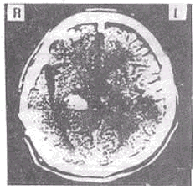

腦CT酒精中毒性神經疾病的中樞神經抑制症狀,應注意與引起昏迷的疾病相鑑別,如鎮靜催眠藥中毒、一氧化碳中毒腦卒中、顱腦外傷等戒斷綜合徵的精神症狀和癲癇發作,應與精神病、癲癇、窒息性氣體中毒低血糖征等相鑑別慢性酒精中毒的智慧型障礙和人格改變,應與其他原因引起的痴呆鑑別。

其它輔助檢查:1.心電圖、腦電圖、腦CT或MRI檢查,有鑑別診斷及中毒程度評估意義;2.肌電圖和神經電生理檢查有鑑別診斷意義。